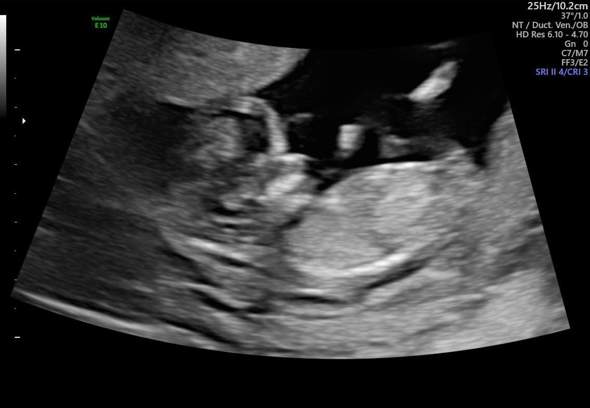

Gebärmutterhalsverkürzung 18 ssw?

Hallo zusammen Ich bin heute 17+2 ssw. Hatte die letzten 4 Tage immer wieder für nur 10-15 Minuten starke Schmerzen im Unterleib die bis zum Rücken strahlten. Ich konnte fast nicht sitzen und dann waren die Schmerzen wieder weg für den ganzen Tag. War dan im KH und sie wussten nicht von wo did Sz kommen aber sagten mir das mein Gebärmutterhals sich auf 2,4 verkürzt hat. Jetzt hat meine FA gesagt ich solle nächsten Montag vorbeikommen. Um es mit ihr anzuschauen. Aber ich habe mich jetzt in Google schlau gemacht und angst bekommen. Ist das wirklich schon soschlimm? Was habt ihr in dieser Situation gemacht? LG